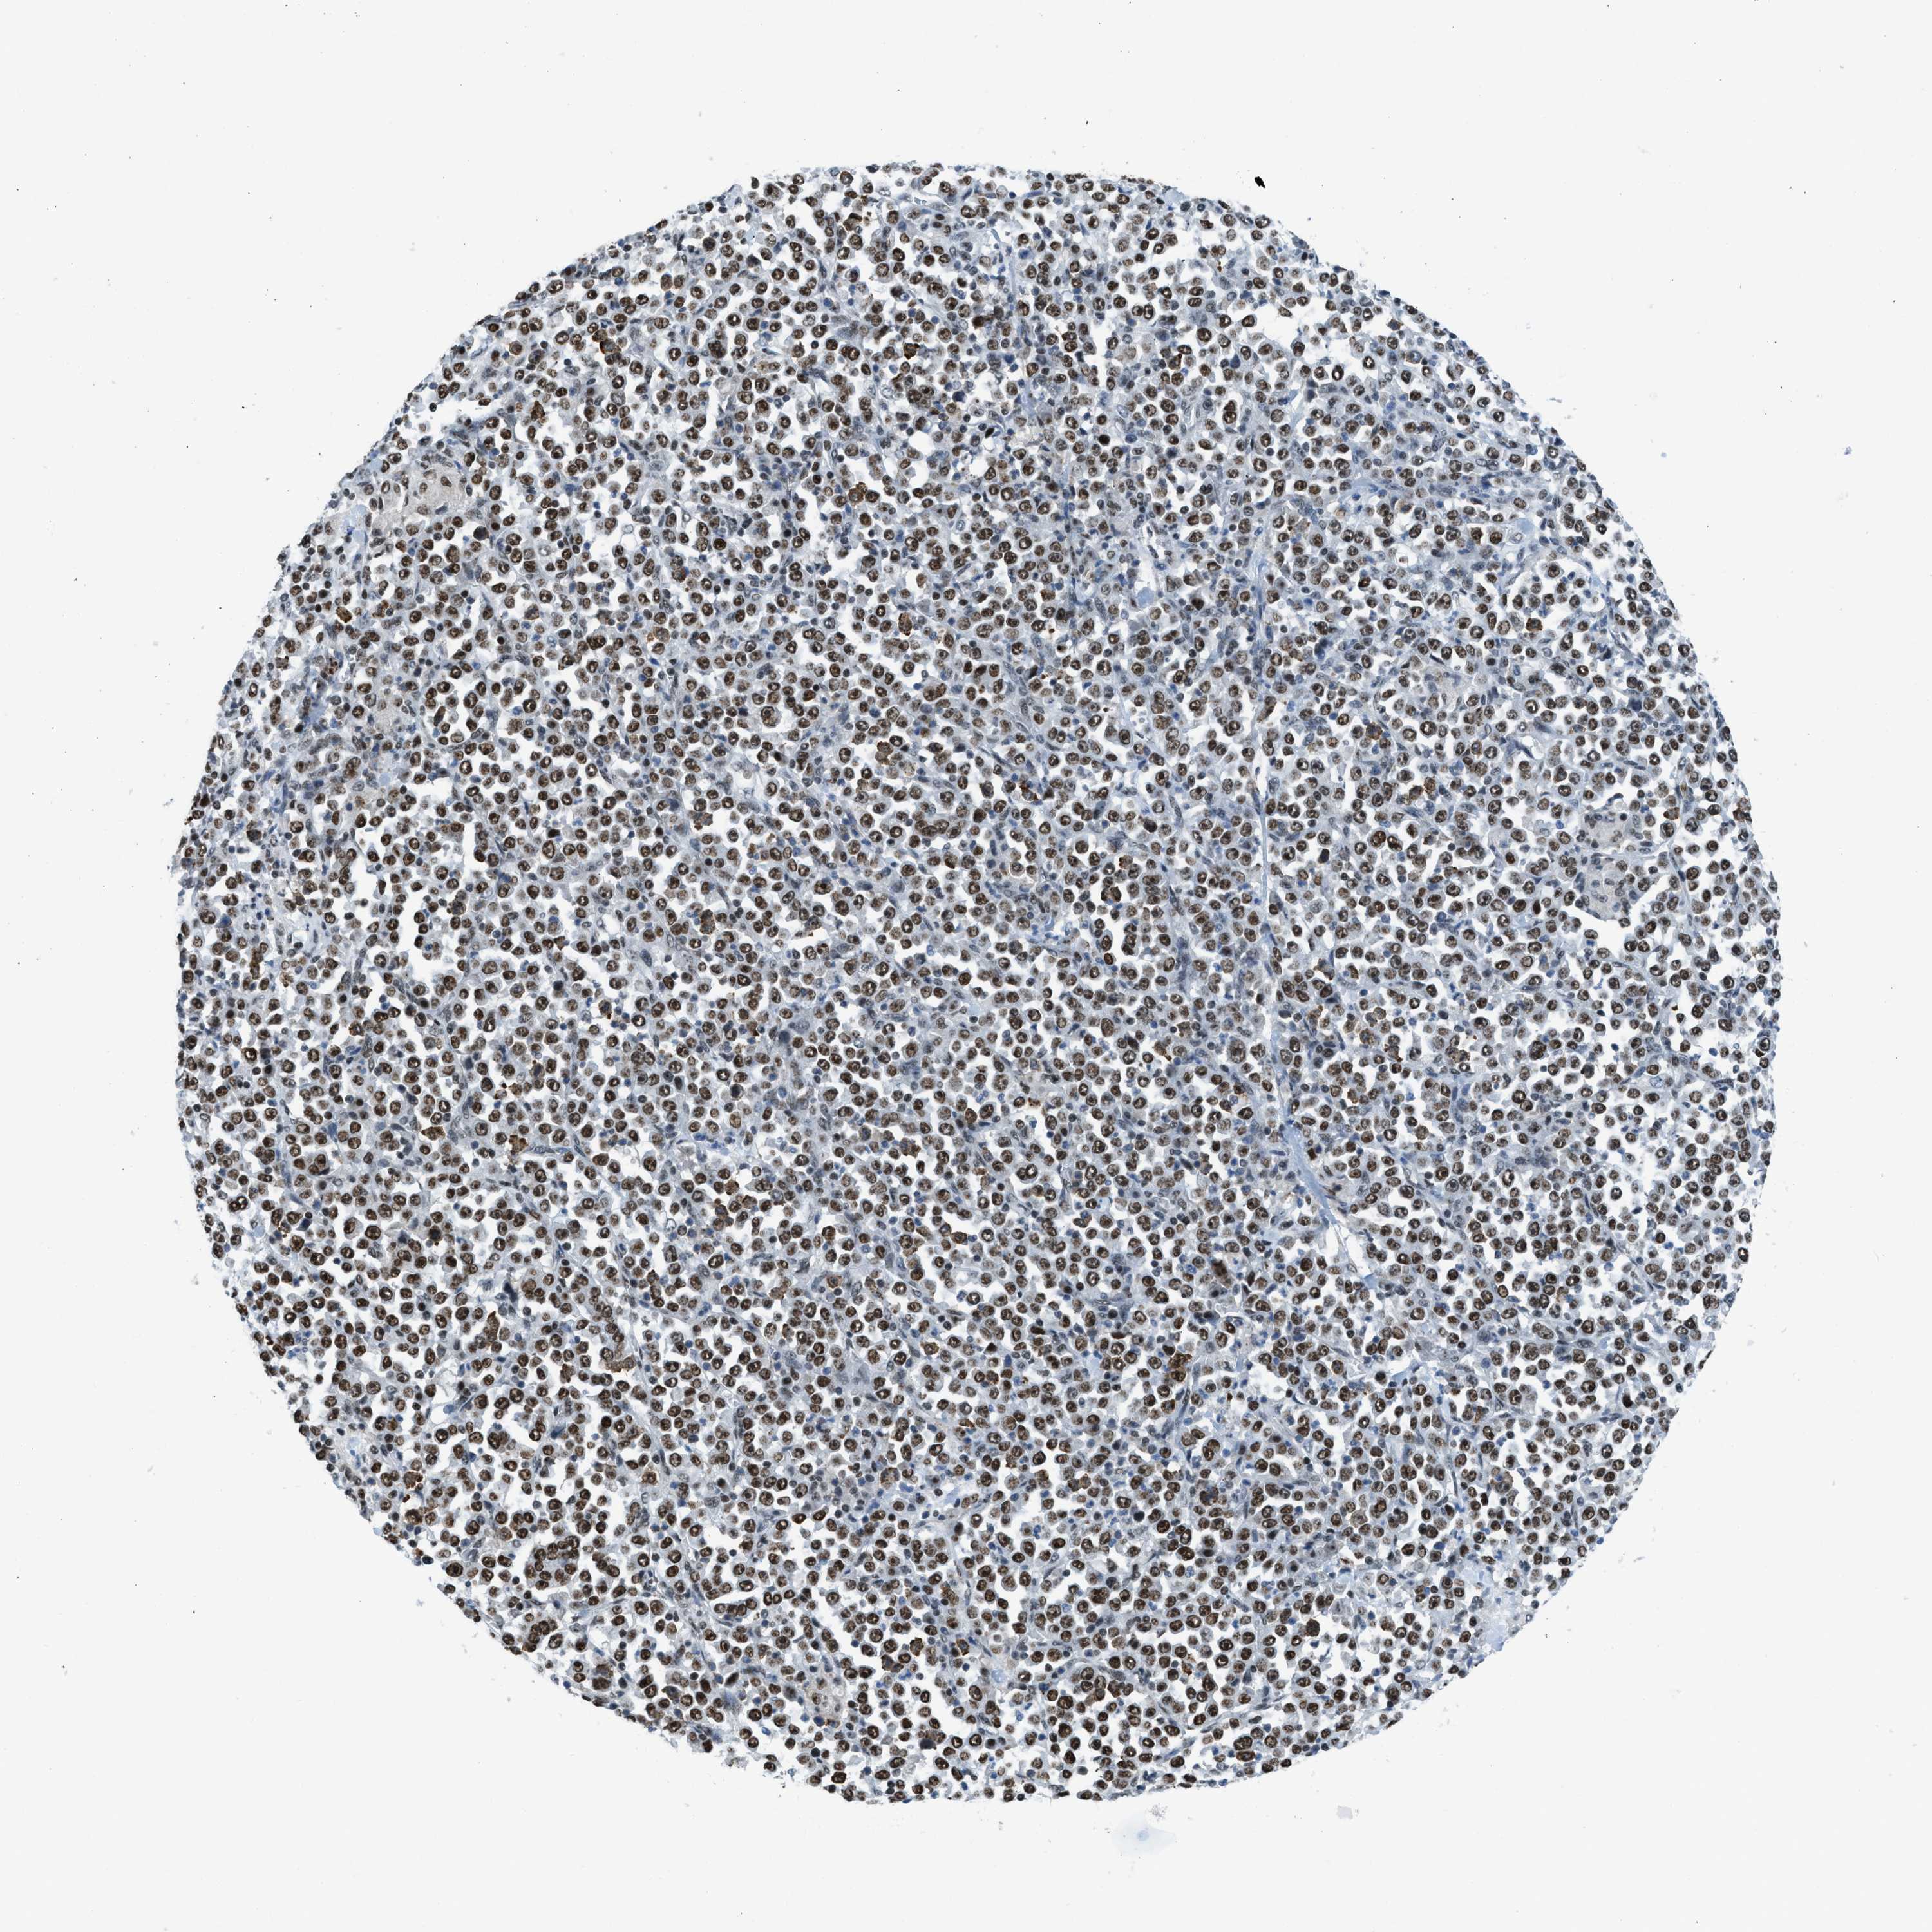

STOMACH CANCER - Protein expressioni

A mouse-over function shows sample information and annotation data. Click on an image to view it in a full screen mode. Samples can be filtered based on level of antibody staining by selecting one or several of the following categories: high, medium, low and not detected. The assay and annotation is described here.

Note that samples used for immunohistochemistry by the Human Protein Atlas do not correspond to samples in the TCGA dataset.

Antibody stainingi

Antibody staining in the annotated cell types in the current human tissue is reported as not detected, low, medium, or high, based on conventional immunohistochemistry profiling in selected tissues. This score is based on the combination of the staining intensity and fraction of stained cells.

Each image is clickable and will lead to virtual microscopy that enables deeper exploration of all samples and also displays staining intensity scores, fraction scores and subcellular localization as well as patient and tissue information for each sample.

Antibody CAB016191

Staining

High

Medium

Low

Not detected

Intensity

Strong

Moderate

Weak

Negative

Quantity

>75%

75%-25%

<25%

None

Location

Nuclear

Cytoplasmic/membranous

Cytoplasmic/membranous,nuclear

Adenocarcinoma, NOS

Adenocarcinoma, High grade